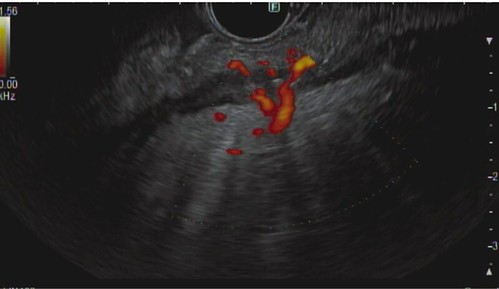

EUS with Doppler demonstrating the feeder arterial vessel.

She subsequently underwent flexible sigmoidoscopy with EUS-guided absorbable gelatin sponge injection to target the culprit vessel with an immediate decrease in Doppler flow. The patient recovered well with no further bleeding episodes.